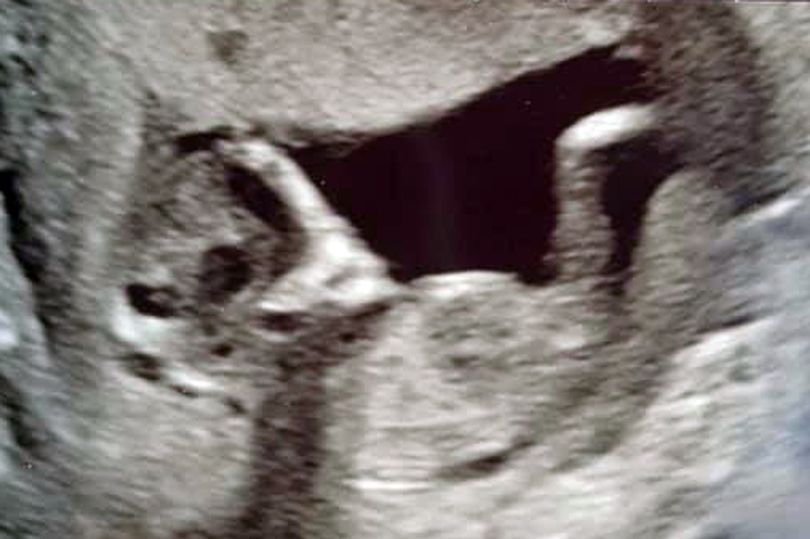

Bakal ibu muda Sophie Scott sudah merasa terkeluar dari dunia ini apabila muka “alien” atau makhluk using muncul dalam imbasan bayinya.

Kegembiraannya untuk membawa pulang seorang bayi comel yang sihat bertukar menjadi panik apabila pasangan Stephen Roberts berkata gambar itu menunjukkan makhluk seperti ET di belakang anak perempuan mereka yang semakin membesar.

Ibu pertama, Sophie, seorang pelajar, South Shields, Tyneside, berkata: “Kami dapat melihat mata tambahan ini di luar bayi dan kepalanya berbentuk seperti makhluk asing.

Empat minggu kemudian imbasan 16 minggu menunjukkan tiada lagi muka makhluk asing tambahan.